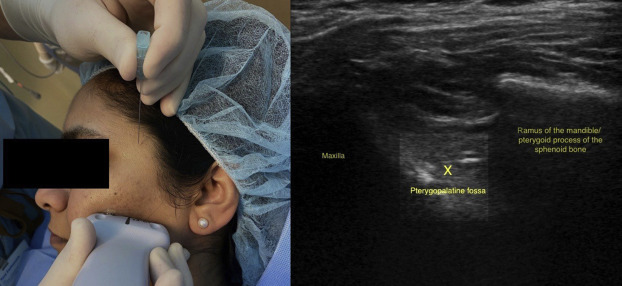

The sphenopalatine ganglion, or SPG, a cluster of nerves nestled behind the nasal cavity, plays a significant role in transmitting pain signals and regulating autonomic functions. By targeting and numbing these nerves, the SPG nerve block procedure can effectively interrupt the cycle of pain and alleviate the debilitating symptoms associated with severe headaches.

The procedure itself was relatively straightforward. The patient was made comfortable, and a local anesthetic was administered to the sphenopalatine ganglion through a specialized nasal device. Within minutes, the numbing effect began to take hold, providing a sense of tranquility and relief.